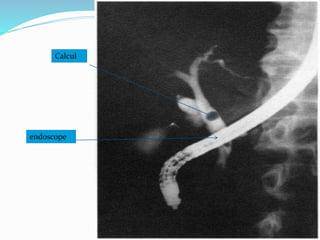

Cholangio-pancréatographie rétrograde par voie

endoscopique:

Elle permet une opacification directe rétrograde de la VBP et

montre les images de calculs, l’état de la VBP et celui du sphincter.

Localise l’obstacle, apprécie sa nature, pose d’un drainage.

La CPRE a en plus de l'intérêt diagnostique un intérêt

thérapeutique, surtout en cas de sujets âgés ou tarés.

Calcul

endoscope